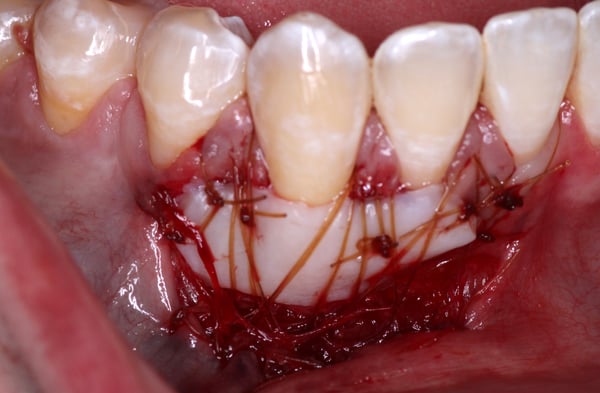

There are many soft tissue grafting techniques that have been proposed that aim to improve soft tissue and achieve an adequate width of keratinized tissue (KT).